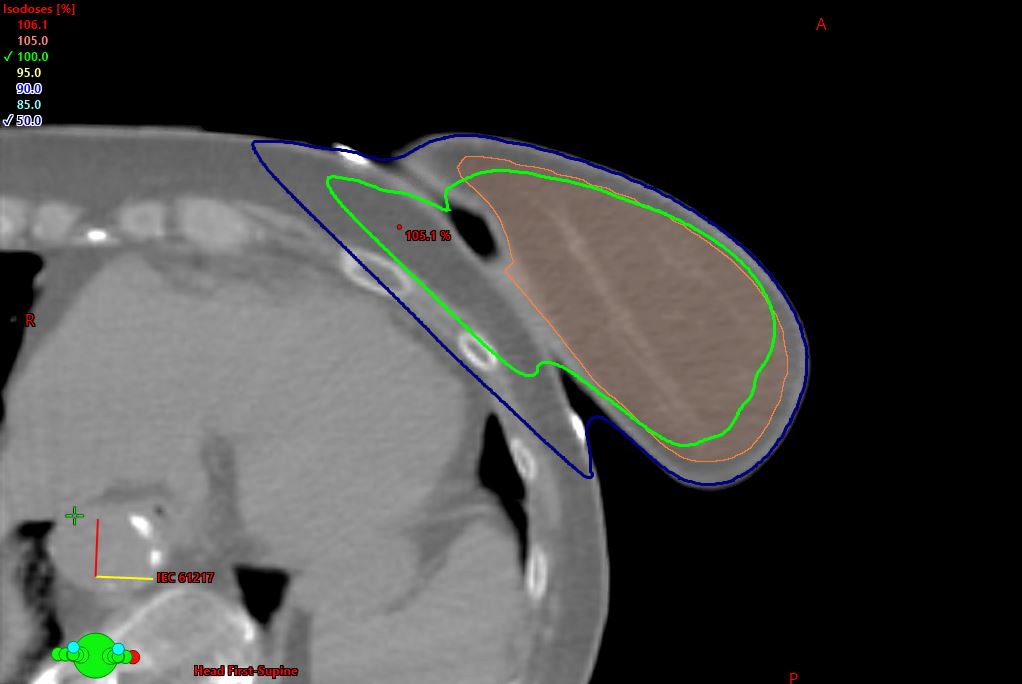

The IMF Breast Wedge™ repositions the breast off the anterior chest wall to reduce lateral fall, ptosis, and the bolus effect of skin-to-skin contact. By minimizing this effect, dose to the inframammary fold is decreased, lowering the risk of reactions such as dermatitis, erythema, or desquamation. Designed by a Radiation Therapist and Physicist, the IMF Breast Wedge is an air-equivalent, easy-to-use device that improves accuracy and patient comfort. Placement is simple—lift the breast, position the wedge at the apex of the fold, and the breast itself maintains the device in place for consistent set-up.

• Air-equivalent design for accurate dose delivery

• Reduces dose to inframammary fold, lung, ribs, and heart